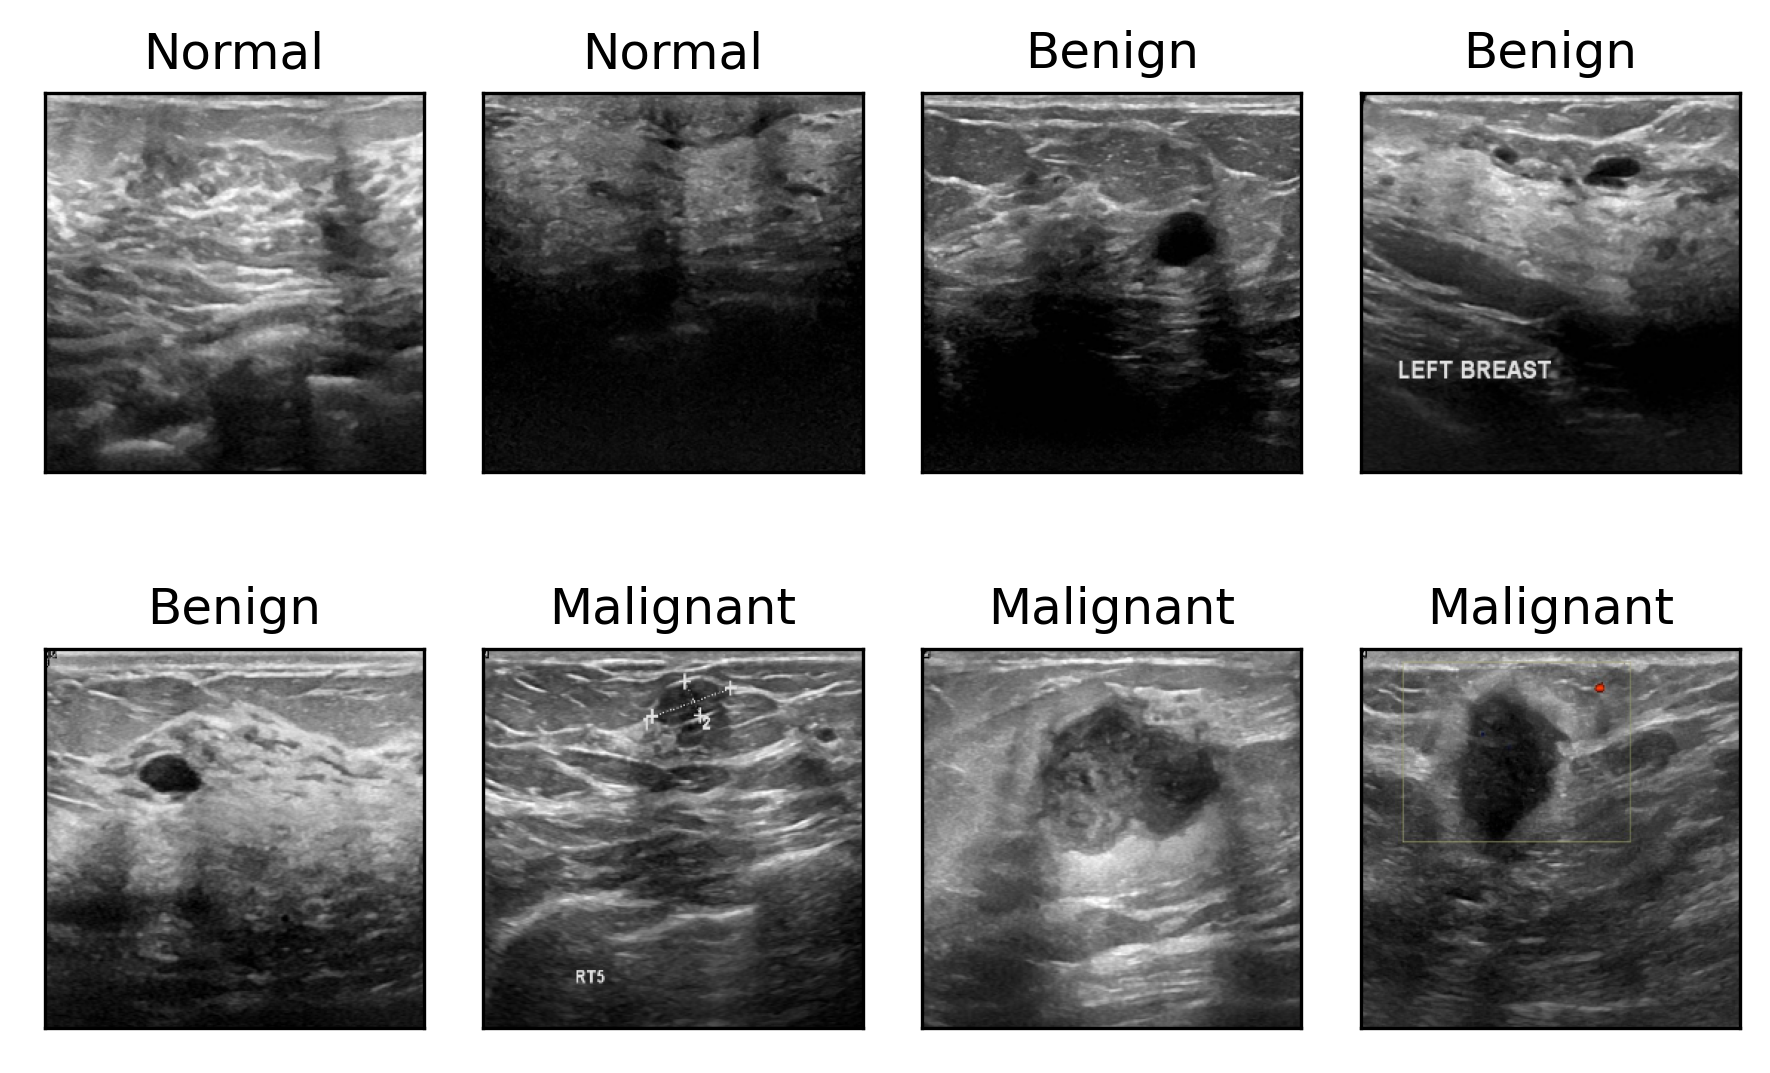

We used the K𝐾K-nearest neighbor algorithm with cosine similarity to obtain 15 similar images from a query image in the image search similarity task. The results are depicted in Figs. 9, 10, 11, and 12 for the Busi, Finger, FG-Net, and Adience datasets, respectively. In the figures, the first column (green box) is a query image, and the remaining columns represent its 15 nearest-neighbor images.

Refer to caption

(a) O𝑂O-Net

(b) S𝑆S-Net

(c) T𝑇T-Net

(d) Q𝑄Q-Net

(e) N𝑁N-Net2

Figure 9: Image similarity search in the Busi dataset with 15 nearest neighbors, the green and yellow boxes represent the query images, and incorrect images, respectively.